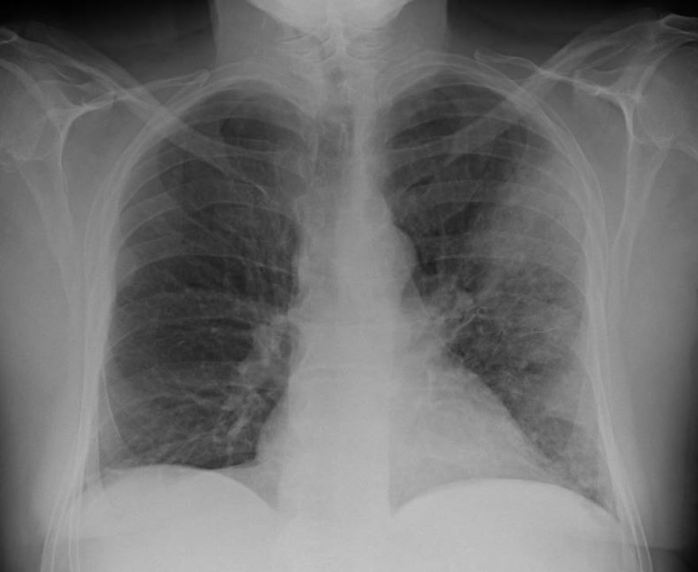

Case one: a 42 yo man with severe alcohol dependence and undiagnosed type 2 diabetes was admitted with fever, dyspnoea and malaise for a week. He was too unwell to drink alcohol and had not spent time in a hot tub or spa bath (nor had he been to a Legionnaires’ conference!). He was hypoxic and hyponatraemia, requiring intensive care support – hi-flow oxygen. His chest X-ray is shown below. He was treated empirically with ceftriaxone and azithromycin and returned a positive urinary antigen for Legionella pneumophila type 1 on the basis of which ceftriaxone was stopped. Blood cultures were negative. He improved with a 7 day course of azithromycin. Unfortunately, he had an inferior ST elevation myocardial infarction a month later which is an increasingly recognised association following severe sepsis.

Case two: a 72 yo man who was previously well was admitted with fever and increasing dyspnoea over 5 days. He had a very mild elevation of his AST and ALT and a CRP of 300. Blood cultures and urinary antigens were negative. His chest X-ray is presented below. On further questioning, he admitted to using a significant amount of potting mix to create a garden over the previous two weeks and had not used a mask. On the basis of this, his benzylpenicillin was ceased and he was continued on azithromycin monotherapy for 5 days. His Legionella longbeachae titre seroconverted from negative on admission to 320 ten days later, confirming the diagnosis.